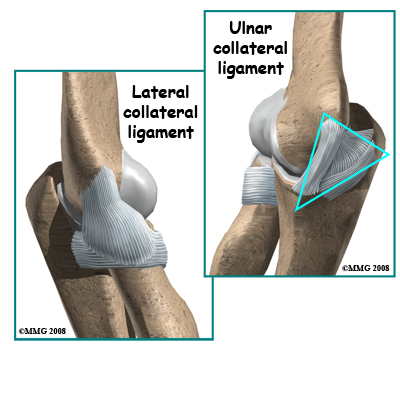

There are several important ligaments in the elbow. Ligaments are soft tissue structures that connect bones to bones. The ligaments around a joint usually combine together to form a joint capsule. A joint capsule is a watertight sac that surrounds a joint and contains lubricating fluid called synovial fluid.

In the elbow, two of the most important ligaments are the ulnar collateral ligament (UCL) and the lateral collateral ligament. The UCL is also known as the medial collateral ligament. The ulnar collateral ligament is on the medial (the side of the elbow that\'s next to the body) side of the elbow, and the lateral collateral is on the outside. The ulnar collateral ligament is a thick band of ligamentous tissue that forms a triangular shape along the medial elbow. It has an anterior bundle, posterior bundle, and a thinner, transverse ligament.

Together these two ligaments, the ulnar (or medial) collateral and the lateral collateral, connect the humerus to the ulna and keep it tightly in place as it slides through the groove at the end of the humerus. These ligaments are the main source of stability for the elbow. They can be torn when there is an injury or dislocation of the elbow. If they do not heal correctly the elbow can be too loose or unstable. The ulnar collateral ligament can also be damaged by overuse and repetitive stress, such as the throwing motion.